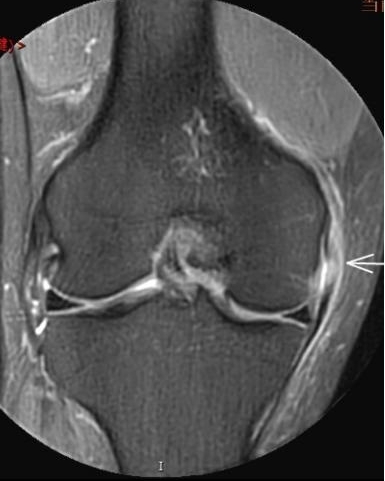

2. 运动后“打软腿”——韧带的“断弦危机”

场景:打球急停后膝盖不稳,走路像“踩棉花”

MRI侦查:揪出前交叉韧带断裂(呈“波浪状”或连续性中断)、内侧副韧带损伤,防止关节“脱轨”

(内侧副韧带损伤)